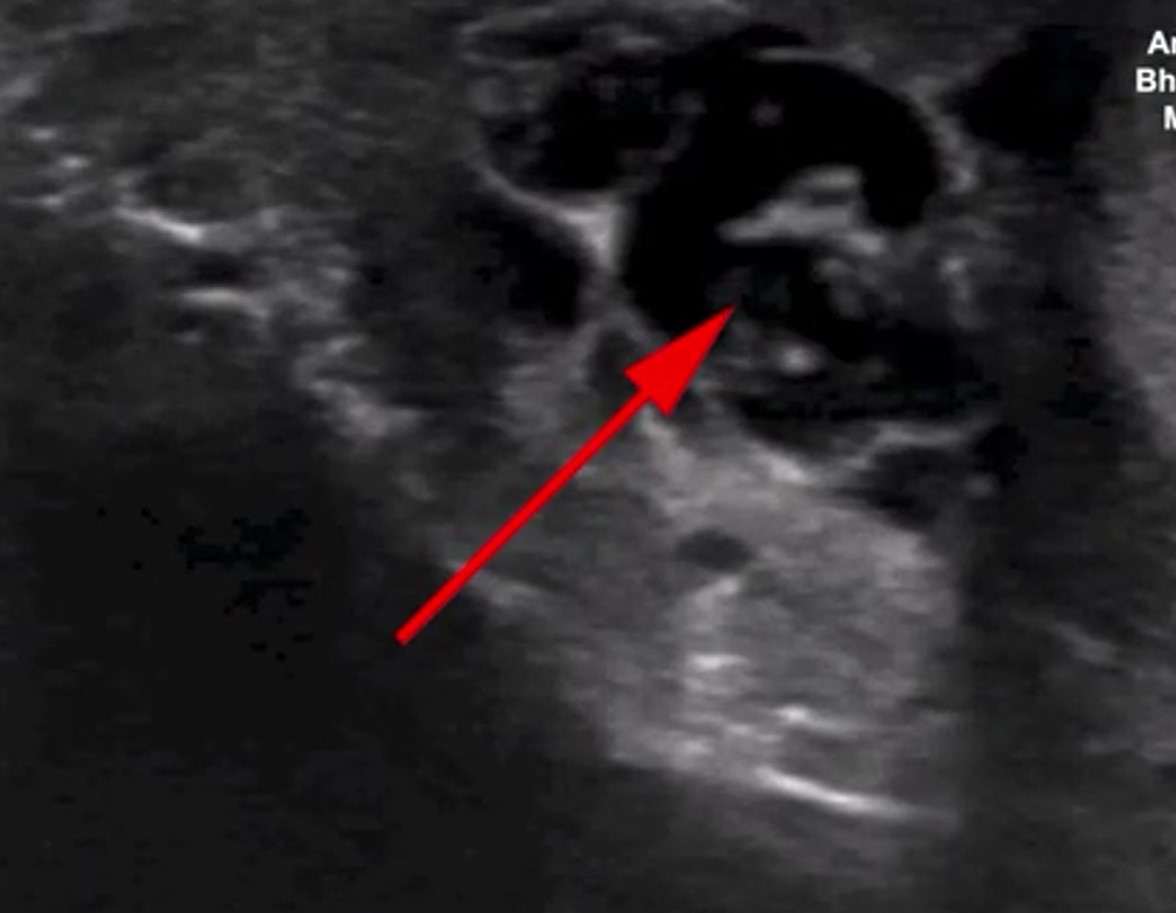

İngiliz Daily Mail gazetesinde yer alan habere göre, doktorlar hastanın skrotumunda hareket eden doğrusal yapılar keşfetti.

Nadir görülen enfeksiyon, New England Journal of Medicine tarafından yayınlanan bir vaka raporu ile ortaya çıktı. Hastayı muayene eden Max Süper Özel Hastanede kıdemli tıbbi danışman olan Dr. Amit Sahu, ultrasonda 'doğrusal yapıların hareket ettiğini' söyledi.

Sahu gözlemledikleri hareket eden doğrusal yapılar için 'dans edecen düzinelerce solucan' ifadesini kullandı. Sahu, 'Lenf sistemine göç ederek kanalların genişlemesine ve işlev bozukluğuna neden oldular' dedi.